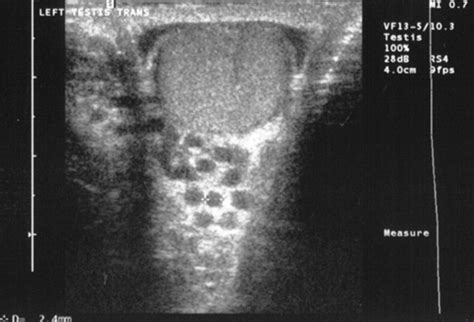

Alright, let’s get down to the nitty-gritty of the transillumination test for varicocele . At its core, this test is all about using light to see through tissues. Think about it like shining a flashlight through your hand in a dark room – you can see the outline and maybe some of the blood vessels. In the context of a varicocele, the doctor will typically perform this test in a dimly lit or dark room. They’ll use a small, bright light source, often a penlight or a specialized transilluminator, and gently press it against the scrotum. The scrotum is the sac that holds your testicles. The idea is that if there’s fluid buildup within the scrotum, like in a condition called a hydrocele (which is different from a varicocele, but can sometimes present with similar swelling), the light will shine through it relatively easily, and you might see a pinkish or reddish glow. This is because fluid transmits light well. However, when we’re specifically looking for a varicocele, the transillumination test has a slightly different interpretation. A varicocele is essentially a collection of enlarged veins, and these veins, while swollen, are generally not fluid-filled in the same way a hydrocele is. Therefore, if the doctor shines a light through the scrotum and sees a lack of significant light transmission, or if the light is blocked by the swollen veins, it can be an indicator that the swelling isn’t due to fluid, but rather to these enlarged veins – a potential varicocele. It’s a quick visual check that, when combined with a physical examination, can give the doctor valuable clues. It’s really one of the initial steps in trying to figure out the cause of scrotal swelling or discomfort. The beauty of this test is its simplicity; it requires minimal equipment and can be done swiftly during a routine physical exam. It’s a fantastic starting point for diagnosis.

So, how does this whole transillumination test for varicocele actually go down? It’s pretty straightforward, guys. First off, you’ll likely be asked to stand up. This is important because varicoceles often become more apparent when you’re in an upright position, due to gravity affecting blood flow. The doctor will then dim the lights in the examination room, creating a darker environment. This darkness is key for the light to be effectively observed. Next, the doctor will take a light source – usually a small, bright flashlight or a penlight – and gently place it against the wall of the scrotum. They might hold it there for a few moments, observing how the light passes through. You might feel a slight pressure, but it shouldn’t be painful at all. The doctor will be looking for a few things. If the scrotum lights up with a clear, pinkish-red glow, it often suggests the presence of fluid, indicating a condition like a hydrocele. But, if the light transmission is significantly blocked, or if you can see distinct, rope-like structures within the scrotum that are obstructing the light, this can be a sign of a varicocele. The enlarged veins themselves don’t transmit light as easily as fluid does. Sometimes, the doctor might also ask you to hold your breath and bear down (this is called the Valsalva maneuver). This maneuver increases pressure within the abdomen and can make varicoceles more prominent, potentially making them easier to spot with the transillumination. It’s a really quick process, usually taking just a couple of minutes. The doctor is essentially using the light to differentiate between fluid-filled swellings and solid or vein-related swellings. It’s a visual aid that complements the tactile examination, helping them form an initial impression about the cause of any scrotal abnormality you might be experiencing. It’s all about using basic physics – how light interacts with different tissues – to get diagnostic information.

Now, you might be thinking, “Why bother with this light test? Can’t the doctor just feel it?” That’s a fair question, and yes, a physical examination is usually the primary way a varicocele is diagnosed. However, the transillumination test for varicocele plays a crucial supporting role, especially in distinguishing between different types of scrotal masses or swellings. The most common scenario where transillumination is particularly helpful is in differentiating a varicocele from a hydrocele. A hydrocele is a collection of fluid around the testicle, and it typically transilluminates (lights up) clearly. A varicocele, on the other hand, is an enlargement of veins, and it usually doesn’t transilluminate well, or the light might be partially obstructed by the swollen veins. By seeing how the light behaves, the doctor can get a quick, preliminary idea of whether the swelling is primarily due to fluid or abnormal veins. This distinction is important because while both can cause discomfort, their underlying causes and potential treatments can differ. For instance, a large hydrocele might require surgical drainage, whereas a varicocele might be managed conservatively or surgically depending on symptoms and fertility concerns. The transillumination test acts as a rapid screening tool. If the test suggests a varicocele, the doctor will then proceed with further examination, possibly including an ultrasound, to confirm the diagnosis and assess its severity. Even if a varicocele is suspected based on touch, the transillumination test can sometimes help the doctor pinpoint the specific areas of concern or rule out other possibilities like cysts. It’s a low-cost, non-invasive, and easily performed test that adds valuable information to the diagnostic process, helping to guide the subsequent steps in evaluating scrotal health. It’s about building a clearer picture of what’s really going on.